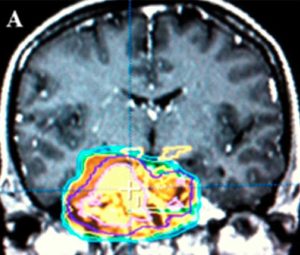

Ressecção cirúrgica de meningiomas petroclivais permanece desafiante devido à localização profunda deles e sua relação vital com estruturas neurovasculares. Embora a história natural desses tumores envolve um curso lento, a incidência de déficits de nervos craniais e a extensão da ressecção tumoral varia bastante na literatura. Algumas revisões desse tópico têm sido discutidas, mas os dados permanecem fragmentados e baseados em séries de casos em retrospectiva, o que atrapalha tentativas de meta-análise. Dentro desse contexto, pesquisa no uso de abordagens minimamente invasivas, incluindo em neuroendoscopias, continua a emergir. O objetivo dessa revisão narrativa é analisar a literatura disponível no tratamento cirúrgico de meningiomas petroclivais, com um foco em tentativas de ressecção com assistência de endoscopia.